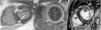

Hypertrophic cardiomyopathy is the most common inherited cardiovascular disease. It is characterized by increased ventricular wall thickness and is highly complex due to its heterogeneous clinical presentation, several phenotypes, large number of associated causal mutations and broad spectrum of complications. It is caused by mutations in sarcomeric proteins, which are identified in up to 60% of cases of the disease.

Clinical manifestations of hypertrophic cardiomyopathy include shortness of breath, chest pain, palpitations and syncope, which are related to the onset of diastolic dysfunction, left ventricular outflow tract obstruction, ischemia, atrial fibrillation and abnormal vascular responses. It is associated with an increased risk of sudden cardiac death, heart failure and thromboembolic events. In this article, we discuss the diagnostic and therapeutic aspects of this disease.